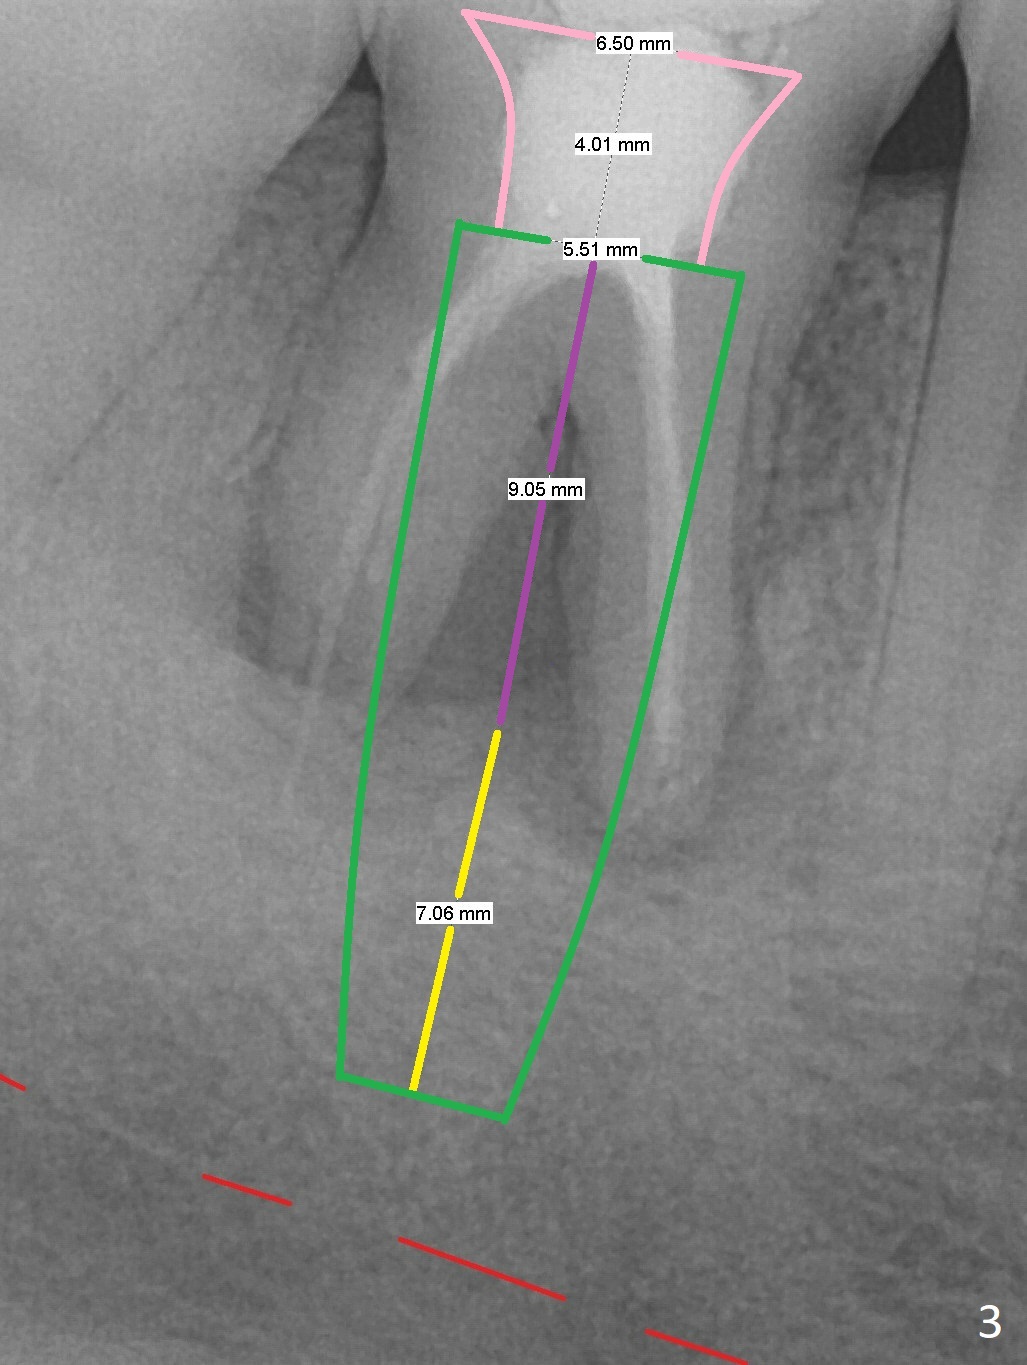

Long Implant

A 34-year-old man has a mobile molar post RCT (Fig.1,3) with lingual gingival recession (Fig.2). Possible bone defect is about 9 mm (Fig.3: purple line). There is approximately 7 mm native bone for primary stability (yellow line). Possible length of the implant to be placed will be 16 mm (9+7). Since the lingual gingiva is recessive (Fig.2), the osteotomy will be initiated more or less in the center of the socket bottom.